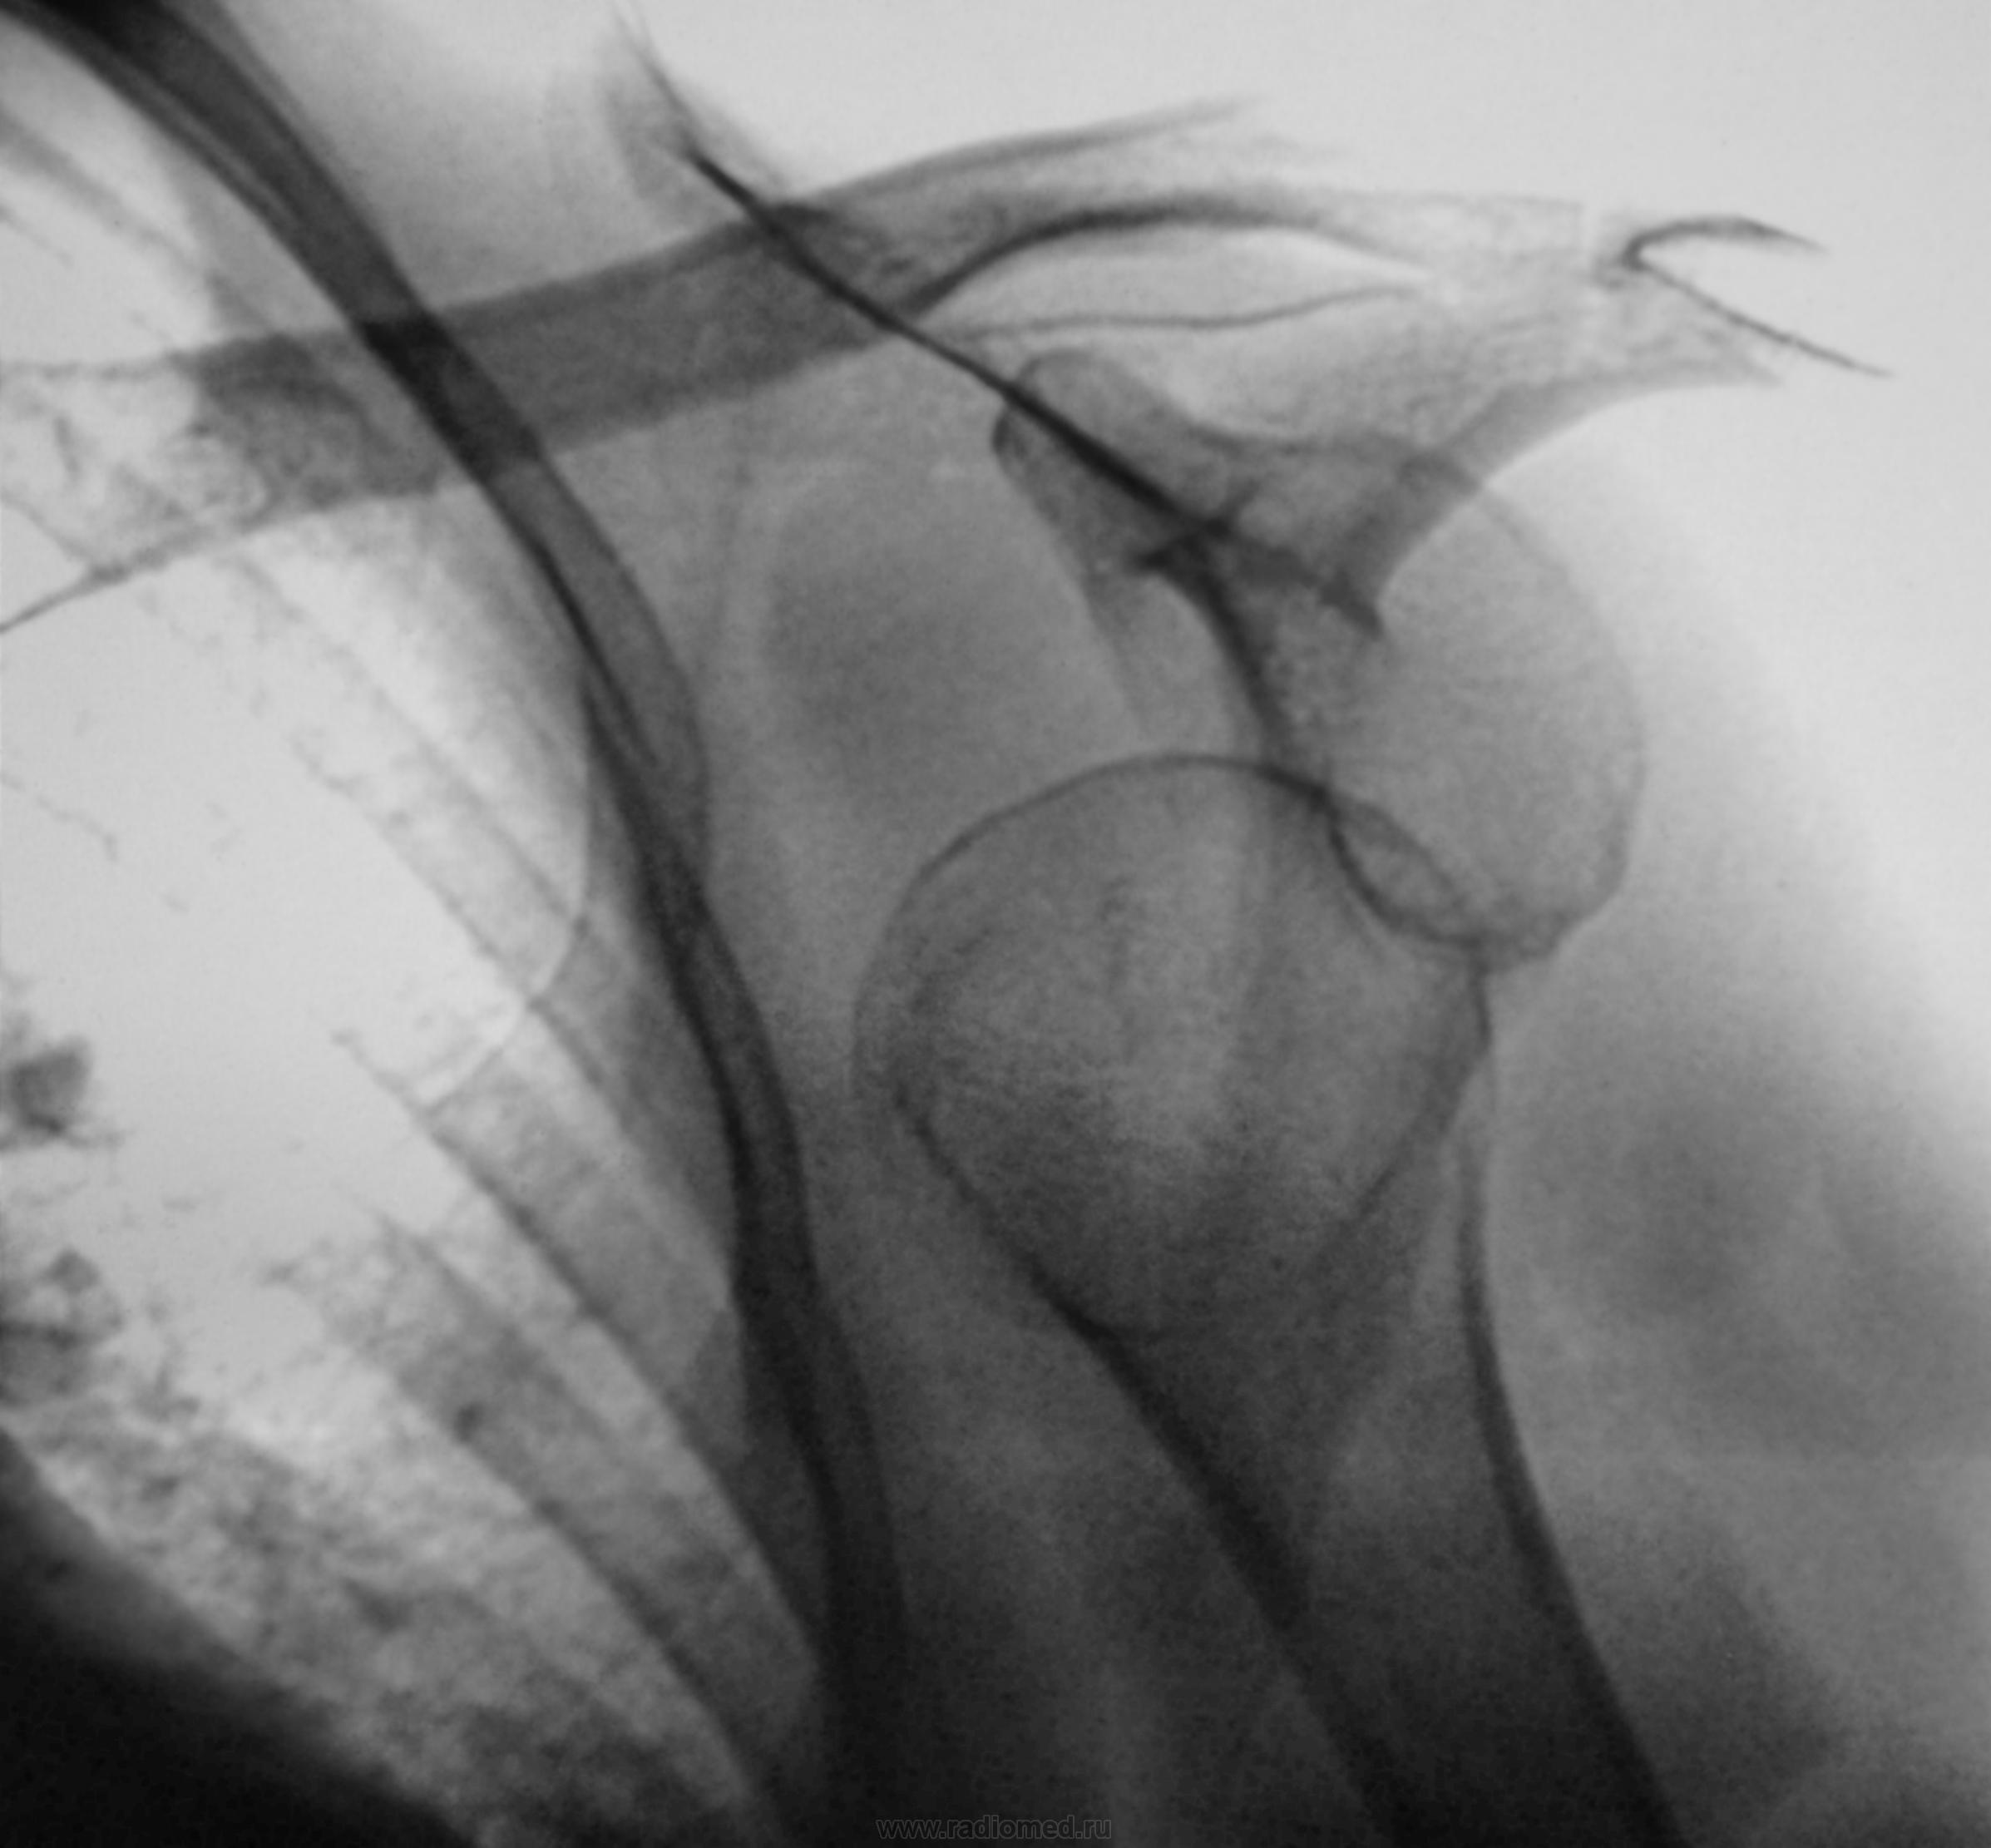

Случай 3.

Но случай 3 был случайной находкой при проффлюшке, да и жалоб никаких...